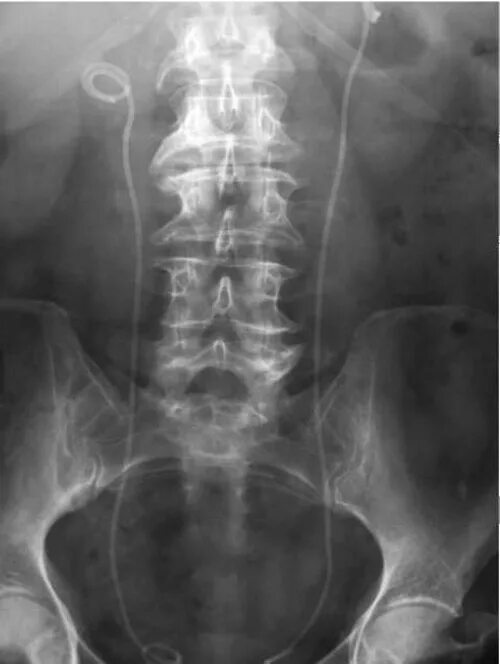

Стенд поставили в мочеточнике